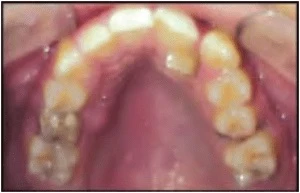

Các răng sau bị xoay chiếm nhiều khoảng hơn. Xoay lại các răng sau có thể giúp lấy lại khoảng. Khoảng trống được lấy lại khác nhau tùy thuộc vào răng liên quan và mức độ xoay. Với một góc xoay như nhau, răng cối lớn chiếm nhiều khoảng hơn so với răng cối nhỏ; trong khi răng trước chiếm ít khoảng hơn.

Hình 6A. Răng sau xoay chiếm nhiều khoảng trống hơn

Hình 6B. Cặp lực được sử dụng để chỉnh xoay

Hình 6C. Hai điểm tiếp xúc ở khí cụ cố định giúp kiểm soát xoay tốt hơn